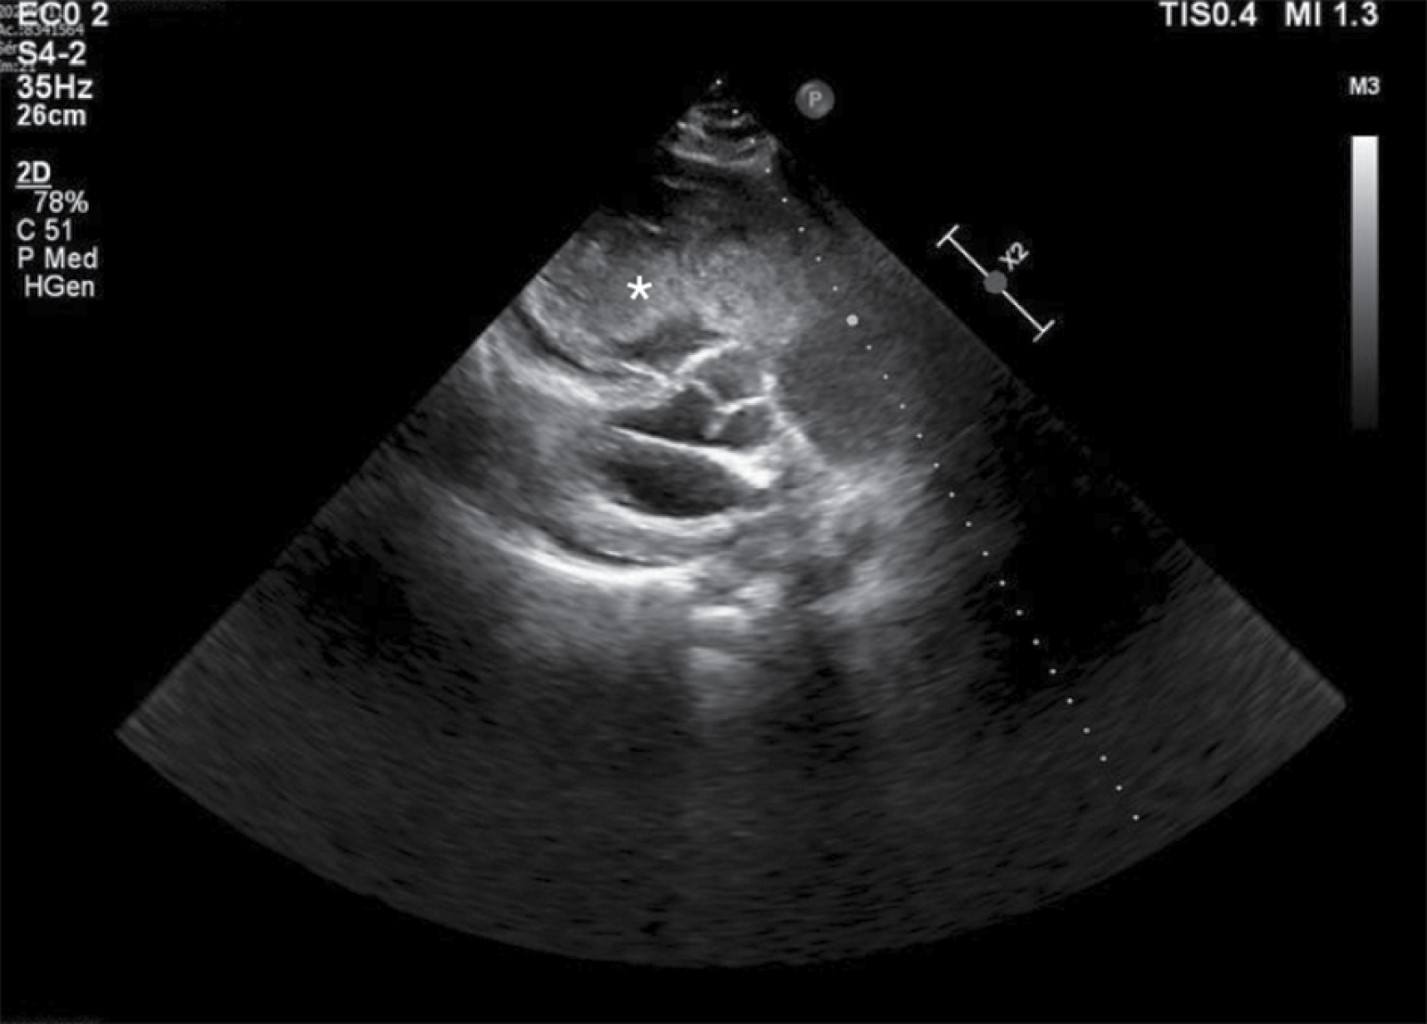

Enorme masa ventricular derecha en un paciente masculino de 25 años

Un joven varón acudió al Servicio de Urgencias del Hospital Santa Marcelina de Cidade Tiradentes con signos de insuficiencia cardíaca congestiva y pérdida de apetito. Se realizó un ecocardiograma bidimensional y se detectó una enorme masa ventricular derecha. Las masas cardíacas son siempre un desafío, y este artículo proporciona una revisión sobre el tema.

Figura 3